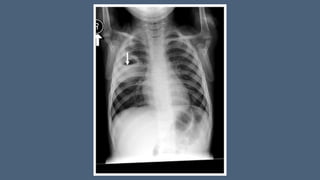

• chest X-ray (a chest radiograph usually detects a thick-walled cavity with an air-

f

luid level,)